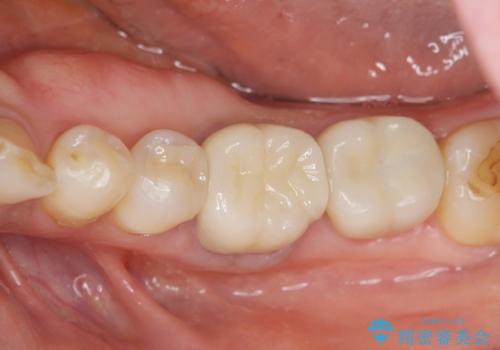

残っている歯を削らないよう、丁寧に除去したのち精密なジルコニアセラミッククラウンで再咬合構成を行っていきます。

見た目の改善が達成できたとともに、皮膚のかゆみも明らかに減少したと喜んでいただくことができました。